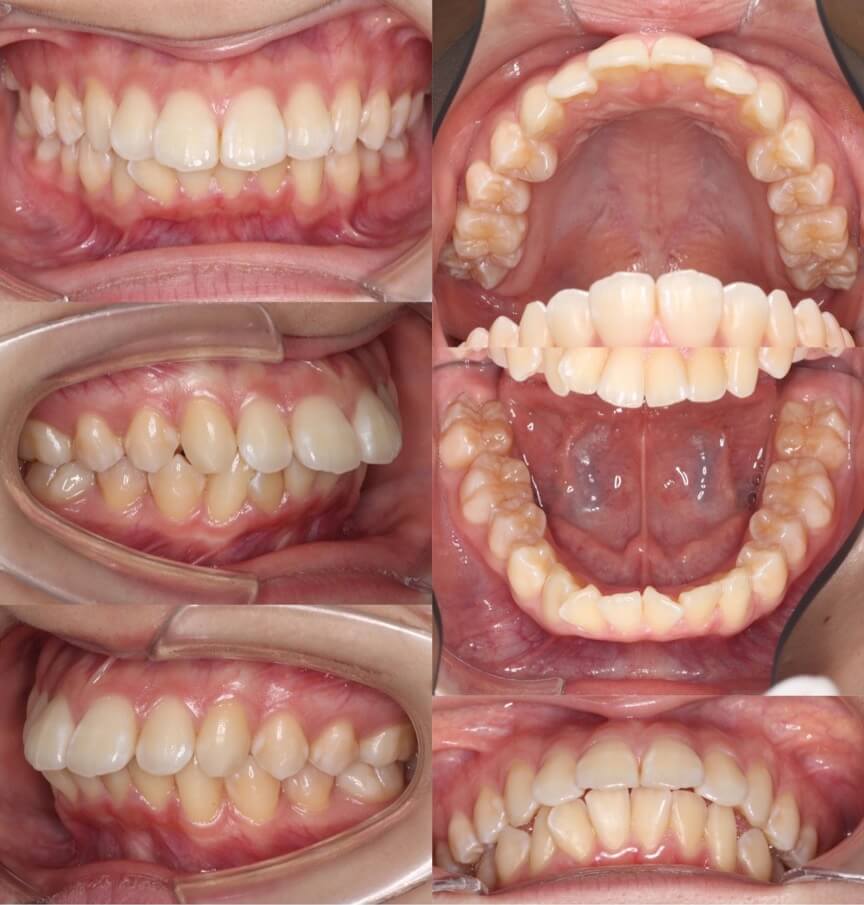

20代女性・マウスピース型矯正装置・上抜歯

このようなII級と呼ばれるかみ合わせの前突症例は、上のみ抜歯を行い、下は非抜歯で治療することが可能です。

<症例概要> 難易度★★★☆☆

主訴:前歯の前突

年齢・性別:20代女性

住まい:千葉県千葉市

症状:叢生・上顎前歯唇側傾斜

治療方針:上顎抜歯空隙閉鎖・下顎歯列後方移動・IPR

治療装置:マウスピース型矯正装置(アライナー装置)

抜歯:上左右4番(計2本)

治療期間:2年0か月

アライナー枚数:58+24+13ステージ(1週間交換)

リテーナー:上下フィックスタイプ+クリアタイプ

治療費用:990,000(税込)

代表的副作用:痛み・治療後の後戻り・歯根吸収・歯髄壊死・歯肉退縮

▶︎その他の副作用

【治療シミュレーション】

上の前歯は抜歯空隙を閉鎖し、下はIPRと後方移動を行うことで前歯の前突を改善させています。